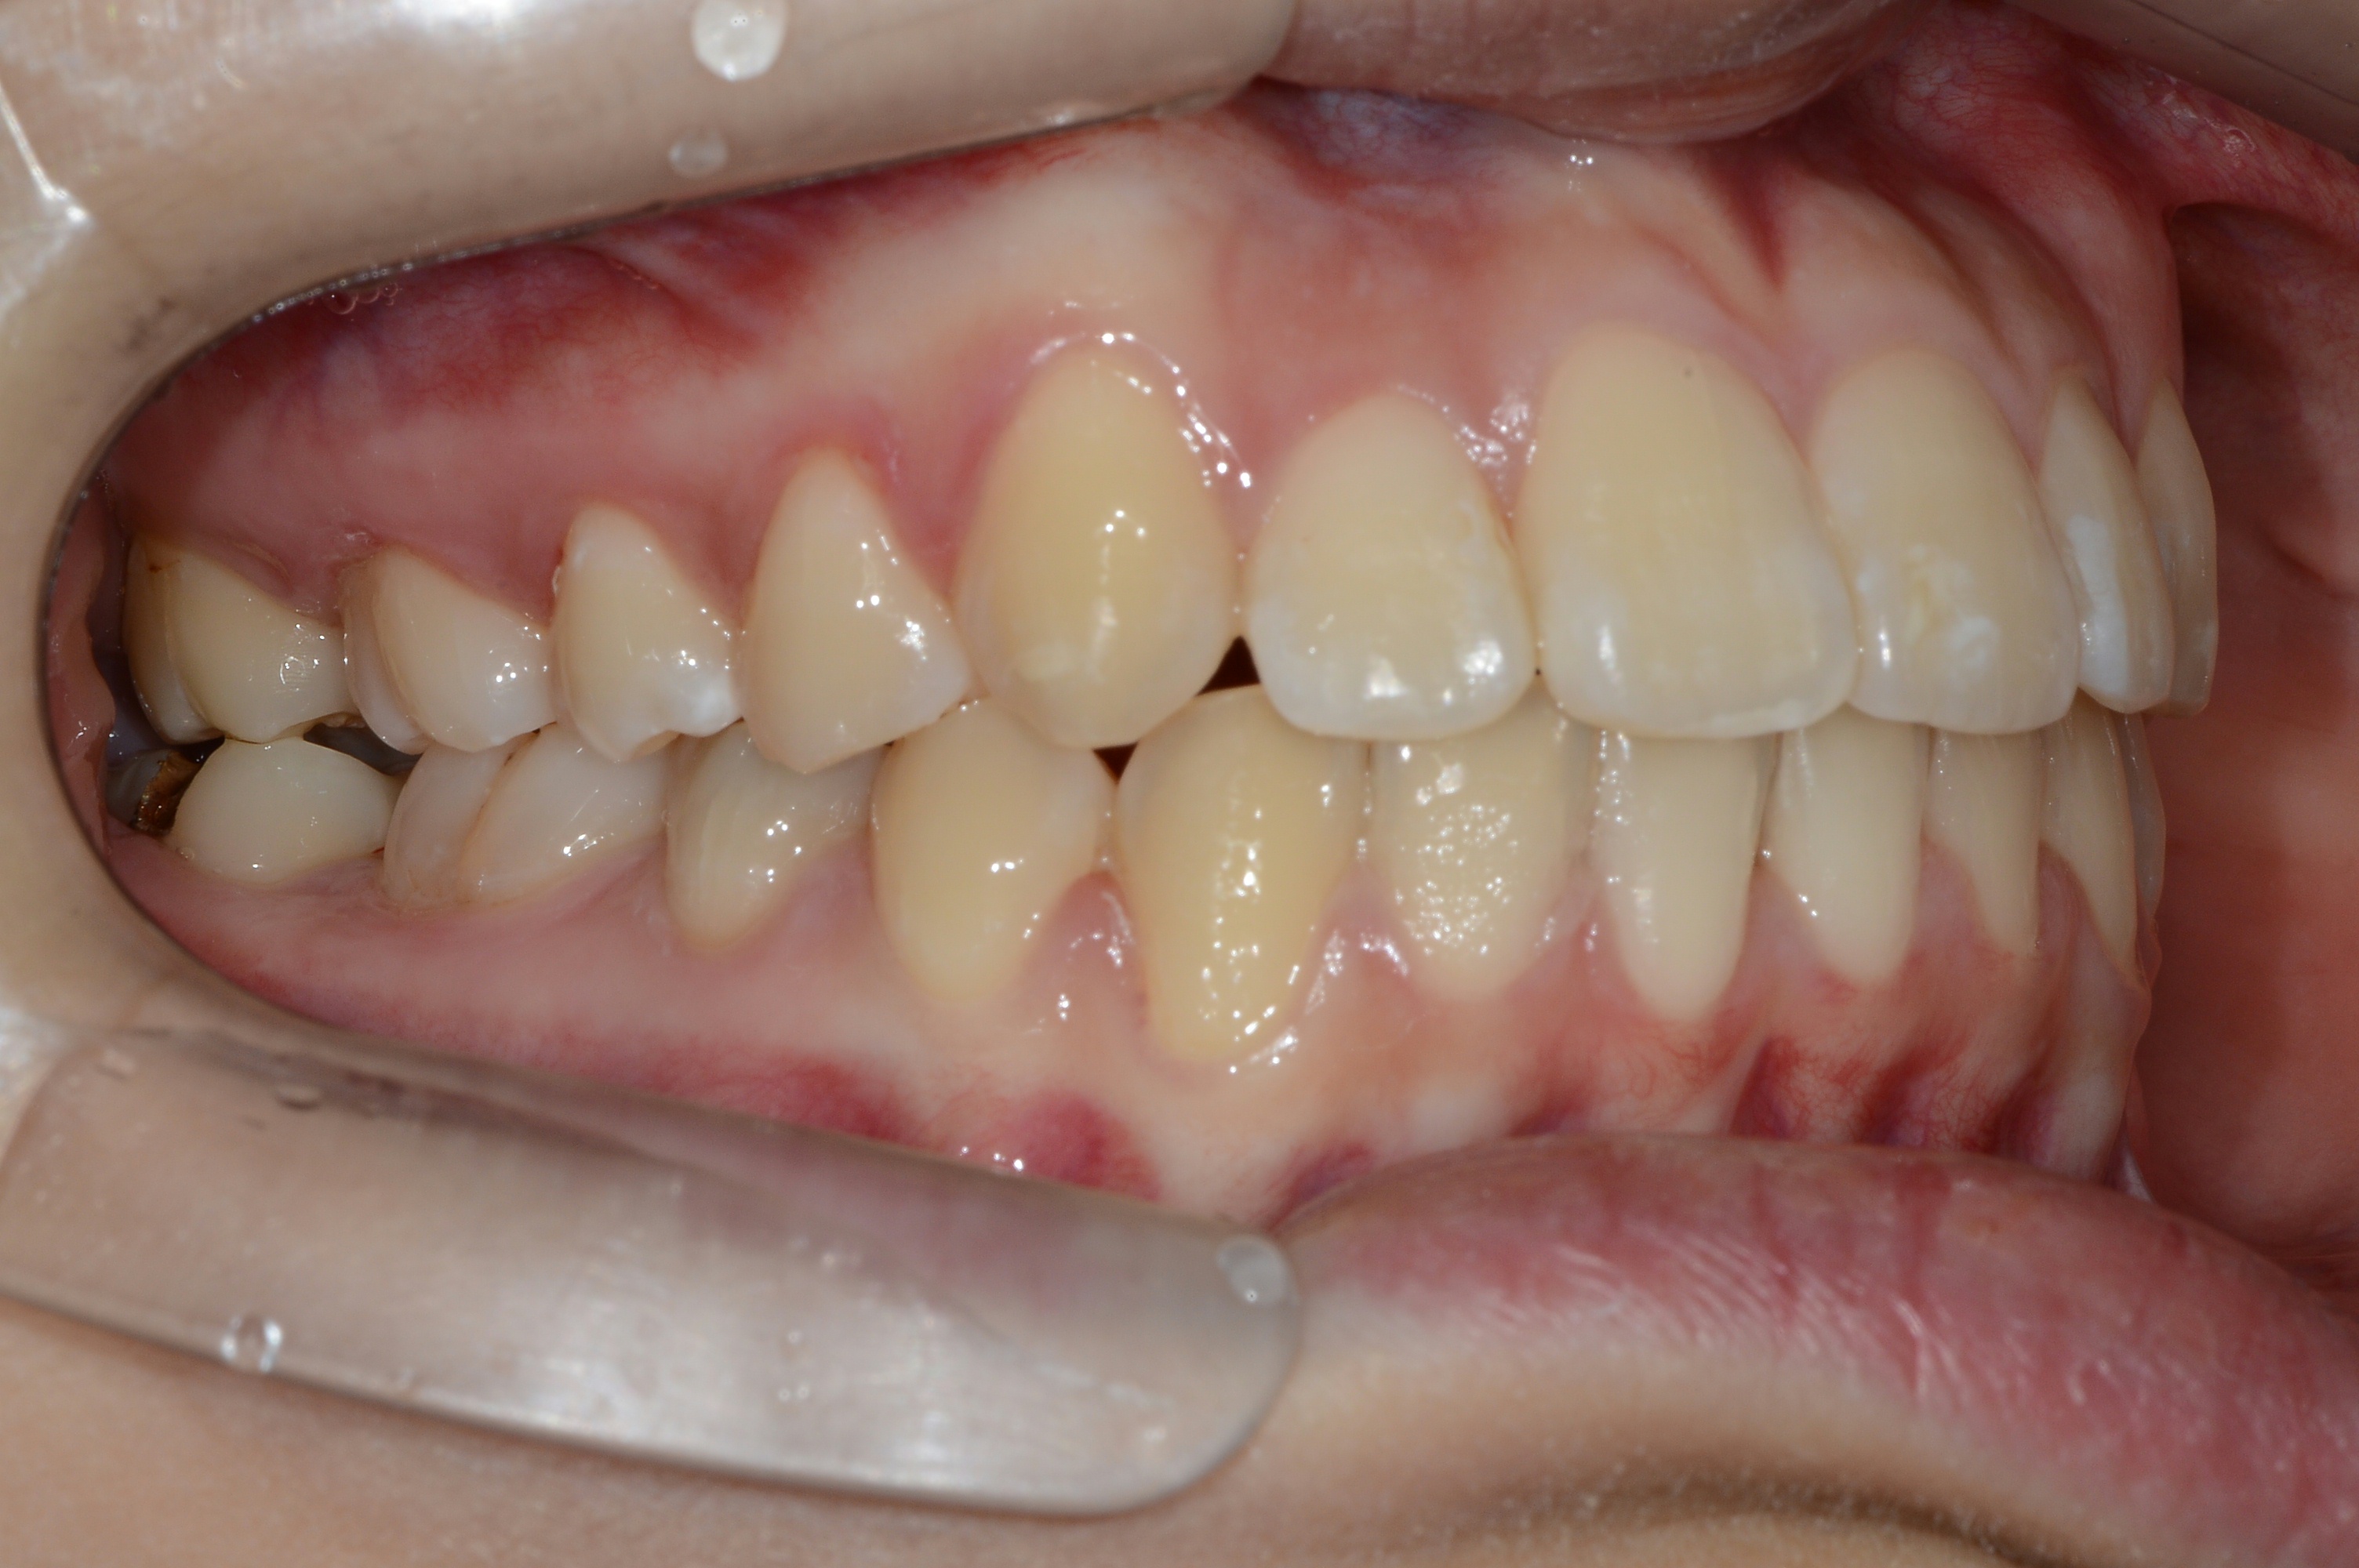

치료 전 사진입니다.